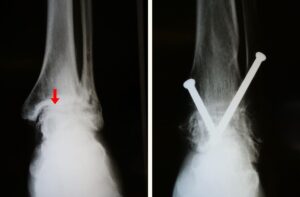

(Left) X-rays show ankle arthritis. Joint spacing narrow (arrow) has resulted in bone rubbing on bone. (Right) A different arthritic ankle after treatment with arthrodesis. Screws are used to hold the bones in proper alignment until the fusion is complete.

Screws are used to fuse the bones of the hindfoot and prevent painful motion.